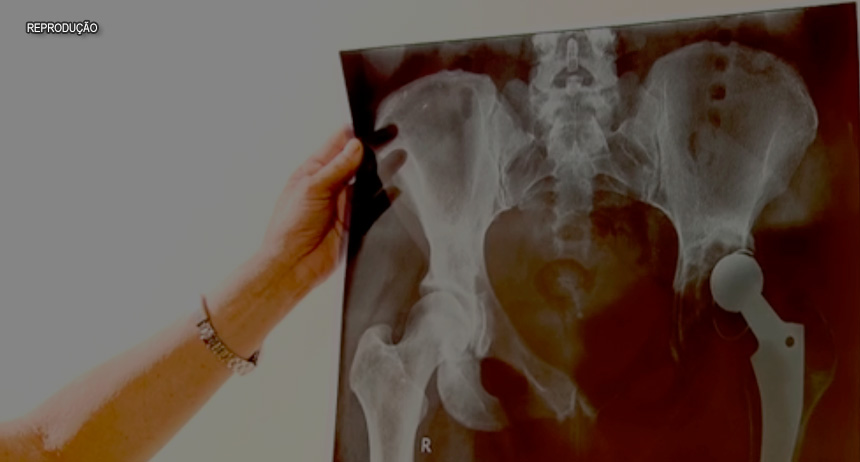

O prejuízo é de R$ 70 milhões. É muito dinheiro e que foi jogado no ralo. Algumas próteses foram compradas incompletas, nem podem ser usadas. Outras, simplesmente sumiram. Foi pouco caso com dinheiro público em todas as etapas, desde a compra, até o armazenamento de materiais cirúrgicos.

Imagens feitas com um celular mostram próteses amontoadas em prateleiras no centro cirúrgico do Hospital do Gama, cidade do Distrito Federal. Já no Hospital do Paranoá a foto revela que parafusos de titânio, usados para cirurgia de coluna, são guardados no chão, próximo ao ralo. No Hospital de Base, no centro de Brasília, as próteses ficam misturadas em sacolas plásticas.